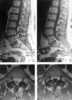

Epidural lipomatosis